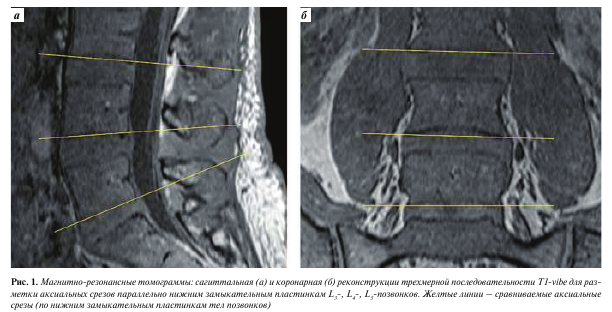

Средний возраст испытуемых составил 43 (±27) года, число мужчин — 8, женщин — 8. Накануне операции всем 16 пациентам проводили МРТ-исследование пояснично-крестцового отдела позвоночника на томографе Siemens Magnetom Prisma 3T по стандартному протоколу. Кроме того, для оценки площади и степени жировой инфильтрации мышц в протокол была включена трехмерная аксиальная последовательность Т1 градиентного эха (T1-vibe) без жироподавления со следующими параметрами: TR — 7 мс, TE — 2,46 мс, FOV — 160 мм, толщина среза — 1 мм, количество срезов — 160, расстояние между срезами — 20 %, угол отклонения — 12°, время исследования — 4 мин 34 с. У 5 из участников исследования использовали аналогичный режим с жироподавлением по методике Dixon (T1-vibe Dixon), для чего было добавлено второе время сбора сигнала эха (TE2 — 3,69 мс), время исследования составило 6 мин. Последовательность с Т1-контраст- ностью была выбрана для оценки жирового замещения, так как и вода (отек), и мышечная ткань на данных изображениях характеризуются низким сигналом по сравнению с жиром, что определяет преимущество этой последовательности для оценки жировой инфильтрации по сравнению с последовательностями с Т2-контрастностью.

Изображения, полученные с помощью вышеописанной последовательности T1-vibe без жироподавления, открывали в программе InobitecPro в режиме мультипланарной реконструкции, где строились аксиальные срезы, параллельные в коронарной и сагиттальной проекциях нижним замыкательным пластинкам L3-, L4-, Ь5-позвонков (рис. 1). На построенных изображениях на всех 3 уровнях с помощью инструмента «ROI полигон» обводили многораздельные мышцы с обеих сторон, как показано на рис. 2 (вдоль границы остистого и суставного отростков, затем по фасции многораздельной мышцы), для оценки средней интенсивности сигнала и площади выделенной зоны. Кроме того, в режиме T1-vibe без жироподавления с помощью инструмента «ROI овал» измеряли среднюю интенсивность сигнала в жировой клетчатке слева от паравертебральных мышц (см. рис. 2).